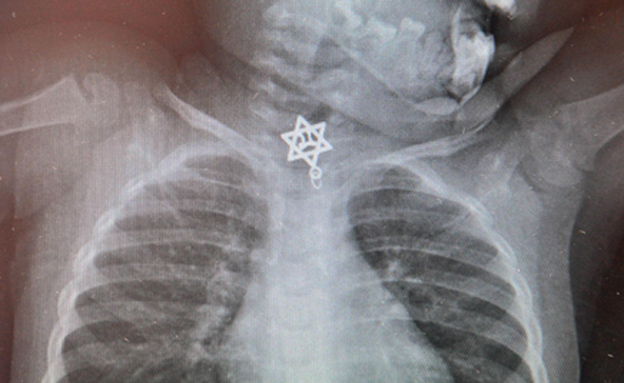

הרופאים בבית החולים קפלן נדהמו לגלות בצילום הרנטגן שביצעו לילדה כי החפץ הזר הוא לא פחות מתליון בצורת מגן דוד עם הכיתוב "חי" בתוכו. רופאה של הפעוטה, ד"ר אודי קצנל סיפר כי "הצורה הגאומטרית עם הלהבים של מגן הדוד שהייתה תקועה לפני הכניסה לוושט בחלק התחתון חייבה שליפה מהירה בחדר הניתוח בהרדמה כללית".

עוד הוסיף ד"ר קצנל: "נערכה תצפית ישירה ללוע ולוושט עם מכשיר אנדוסקופי עדין שאפשר זיהוי וחשיפה בצורה בטוחה של הגוף הזר, והוצאתו בזהירות ובעדינות רבה בסיוע של מלקחיים מיקרו כירורגיים. כעת, לאחר הוצאת מגן הדוד תוכל טליה לחזור לתפקוד רגיל ושגרתי".